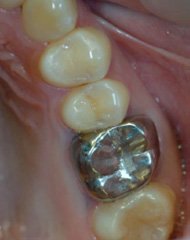

この方のお口の中の状態が、左上の写真です。このような金属の被せ物をご使用中の方もいらっしゃるかと思います。

これらの銀歯と土台を除去してみると、内部が黒く変色していることが確認できました。変色部分と金属の被せ物を丁寧に除去し、金属を使用しない被せ物に置き換えました。